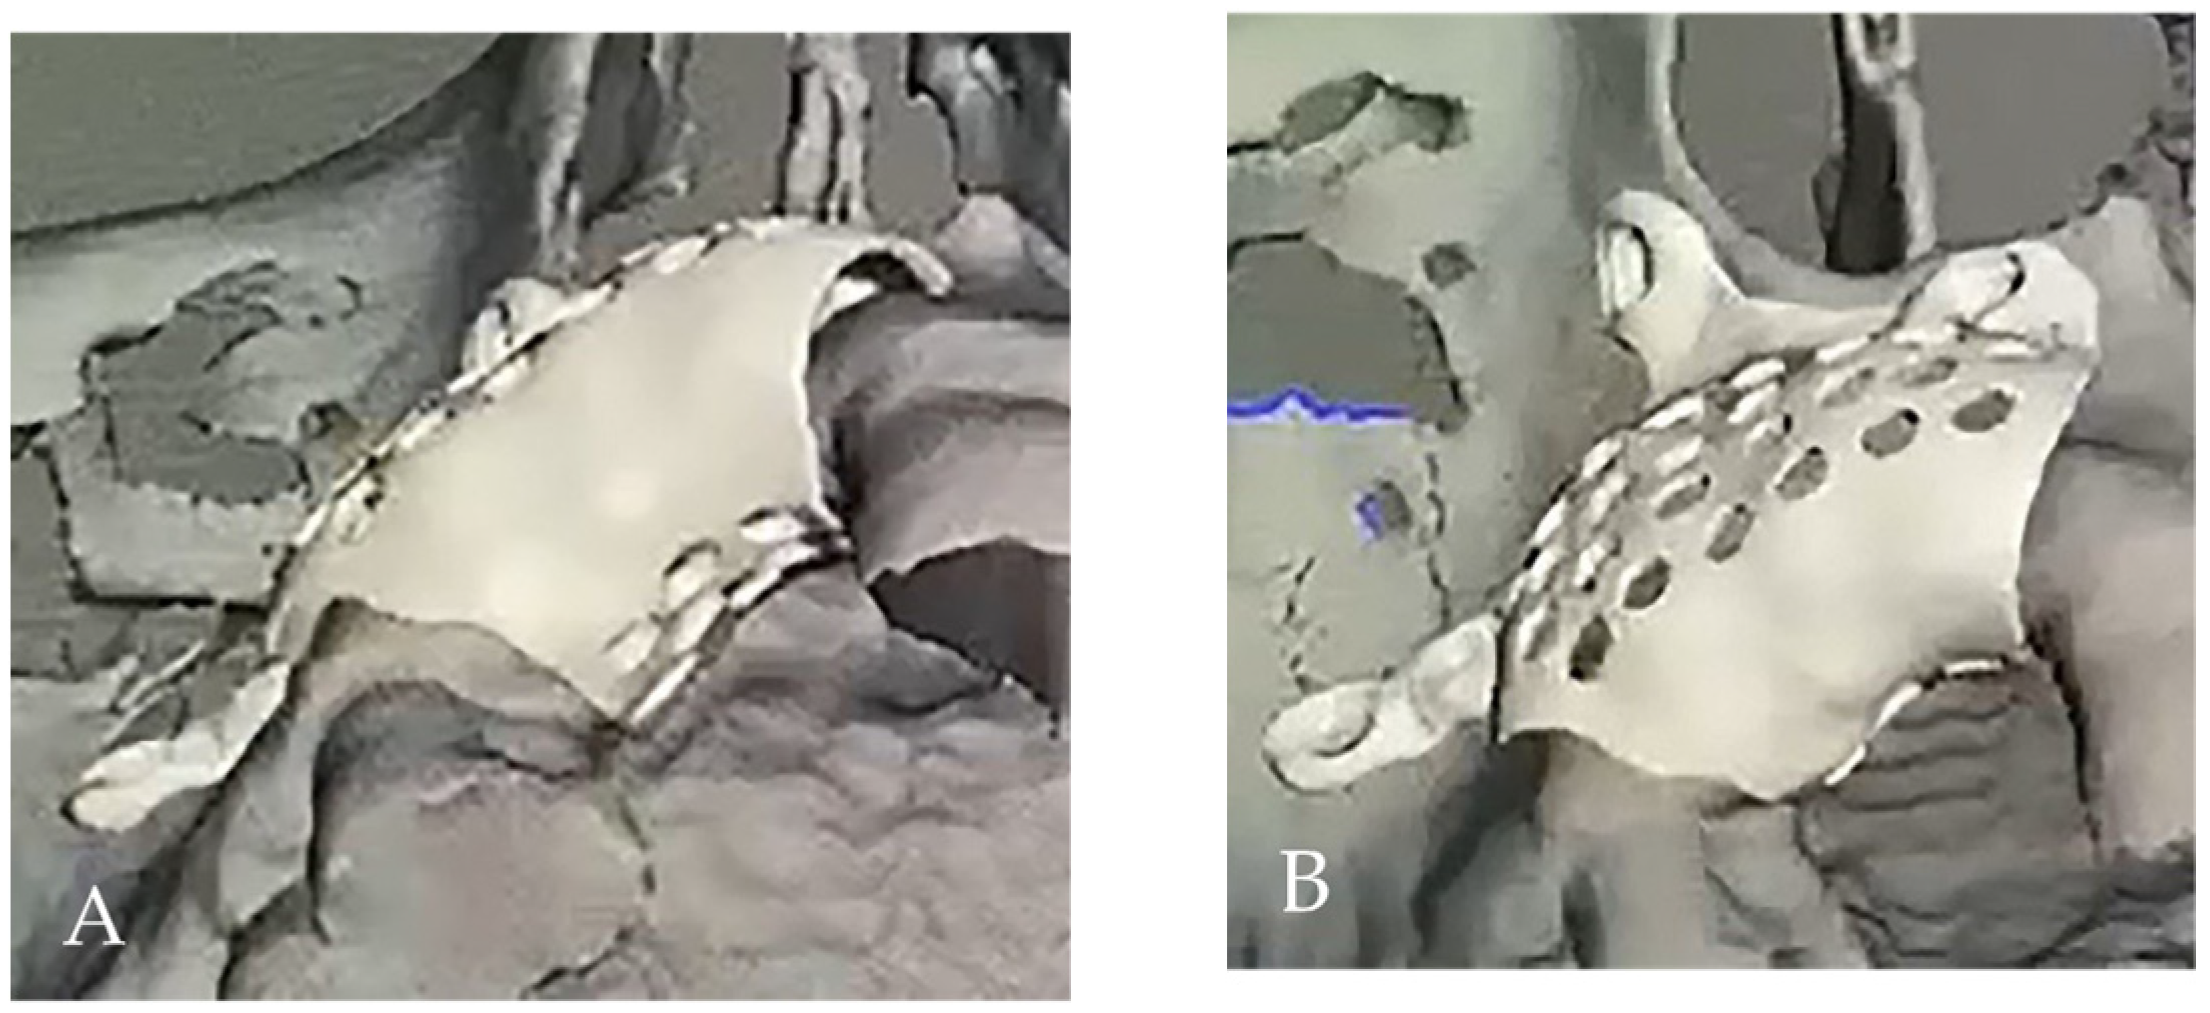

The digital model was obtained by converting the DICOM to STL-format file. Using dedicated software EXOPLAN (exocad GmbH, Darmstadt, Germany), the 3D reconstruction of the patient’s titan mesh was designed, giving the final desired form (including holes and screw holes). Then STL file of the mesh was exported to Local 3D Printing Center and printed using selective laser melting (SLM) technology (Mysint100, SISMA, Piovene Rocchette, Italy) of titanium powder (Figure 4A,B and Figure 5A,B).

Figure 4. The digital design: (A) occlusal view, (B) palatal and buccal view.